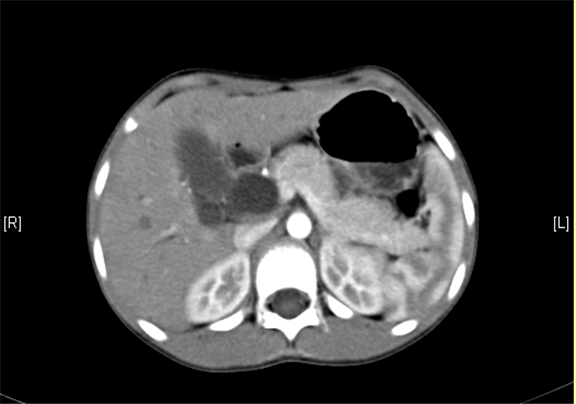

上腹部增强CT:肝内外胆管扩张,考虑胆管囊肿(以左右肝管、肝总管及胆总管扩张明显)可能性大。

术前CT检查:

静脉期